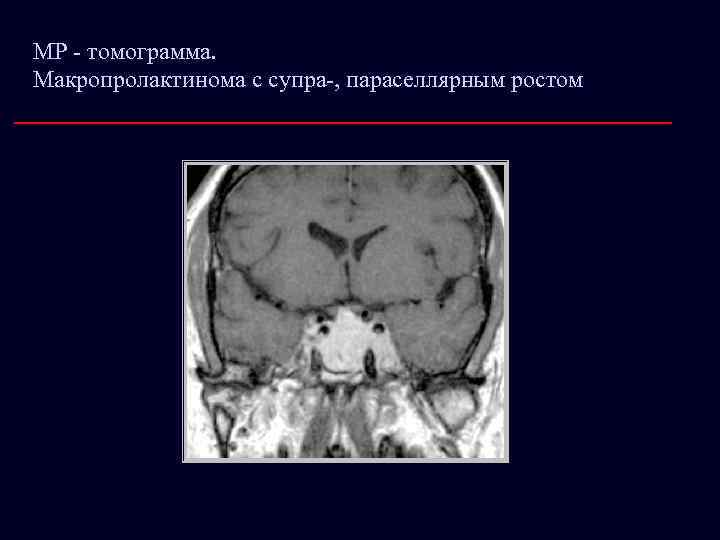

МР - томограмма. Макропролактинома с супра-, параселлярным ростом